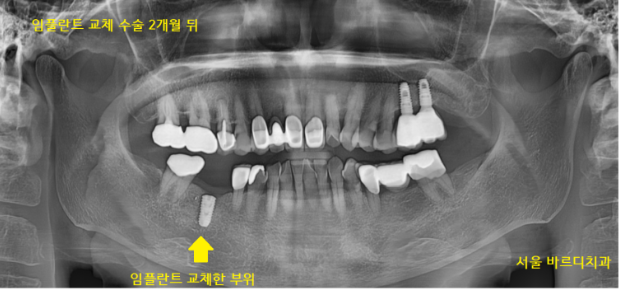

230406

임플란트 교체 후 2개월 뒤 체크

230613